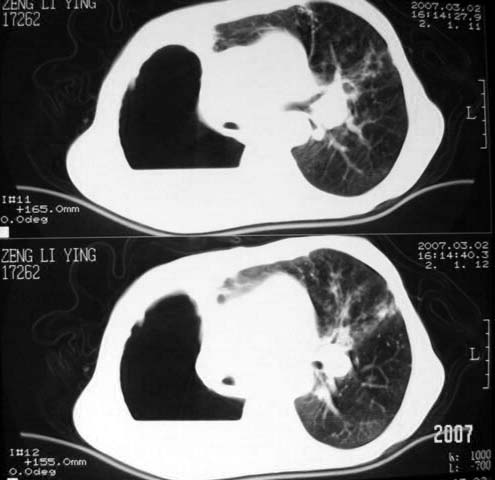

以下是引用dyqct在2007-3-2 22:04:00的发言:[br]考虑:1、右侧毁损肺伴支气管胸膜瘘(多条支气管与胸腔相通、液气胸);[br] 2、左肺浸润型肺结核。[br][br][br][br]